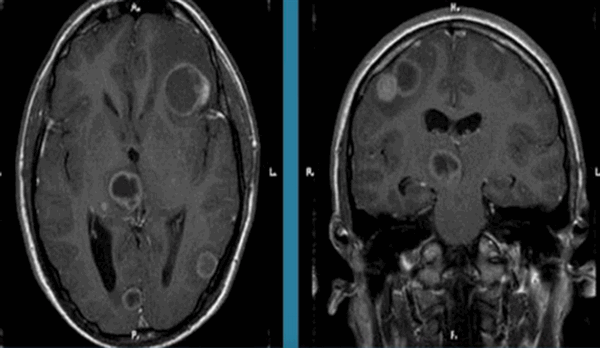

Токсоплазмоз на МРТ головного мозга

Магнитно-резонансная томография является безболезненным и информативным способом исследования головного мозга. Послойное МР-сканирование позволяет детально рассмотреть все участки органа, оценить их структуру. С помощью определенных последовательностей можно подробно изучить белое и серое вещество, сосуды, желудочковую систему.

МРТ считают эффективным методом выявления очаговых поражений мозга. К таковым относят ограниченные участки с нарушенной структурой внутри вещества органа. Подобные изменения часто сопровождаются масс-эффектом, отеком, деформацией окружающих областей. Очаги в головном мозге на МРТ выглядят как зоны изменения МР-сигнала. По специфическим признакам, локализации, размерам и степени влияния на окружающие структуры рентгенолог может сделать предположения о характере патологии. Пользуясь перечисленными сведениями, врач ставит диагноз, составляет для пациента прогноз и подбирает лечение.